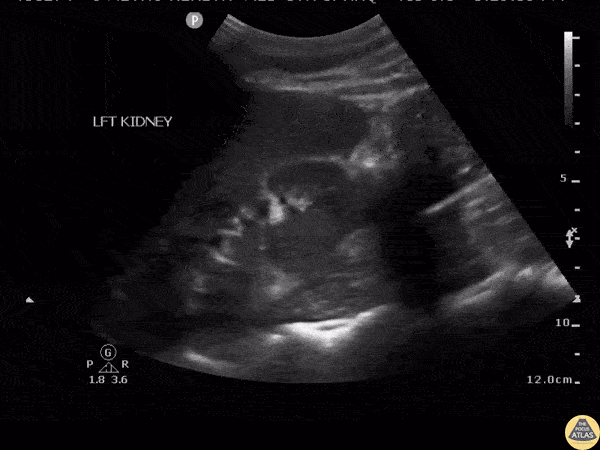

Longitudinal view of the kidney representative of a renal abscess. Note the heterogenous cystic structure within the renal cortex. Image courtesy of Robert Jones DO, FACEP @RJonesSonoEM Director, Emergency Ultrasound; MetroHealth Medical Center; Professor, Case Western Reserve Medical School, Cleveland, OH View his original post here